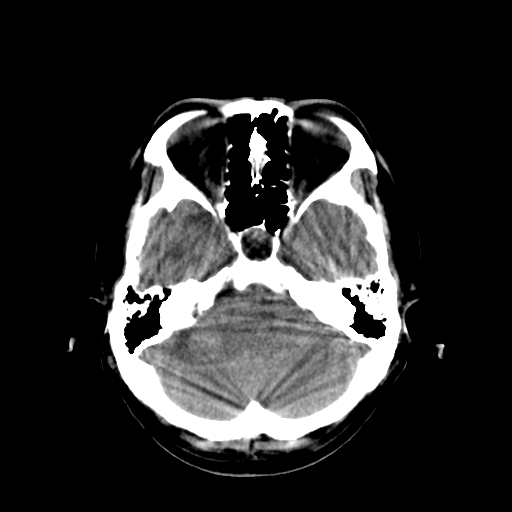

男,34岁,头痛数天。请大家看看是否有占位.

脑干、右侧桥臂及右侧小脑半球可见等低混杂密度影,环池部分闭塞,小脑上池及第四脑室受压移位、闭塞,考虑占位性病变可能性大,胶质瘤?室管膜瘤?不除外脑神经如听神经瘤及梗塞等,建议上传骨窗

疑右侧听神经瘤并梗阻性脑积水,空蝶鞍。建议行ct增强扫描检查。

(请上传骨窗——右侧内听道感觉不正常)

脑干、右侧桥臂及右侧小脑半球可见等低混杂密度影。轻度脑积水。考虑右侧桥臂区域占位性病变。建议mri检查。

右侧桥小脑区见等混杂密度占位影,病变境界不清,环池部分闭塞,四脑室受压左移,建议上传增强或mr检查片...

以下是引用余辉在2008-11-17 12:51:00的发言:[br]脑干、右侧桥臂及右侧小脑半球可见等低混杂密度影,环池部分闭塞,小脑上池及第四脑室受压移位、闭塞,考虑占位性病变可能性大,胶质瘤?室管膜瘤?不除外脑神经如听神经瘤及梗塞等,建议上传骨窗